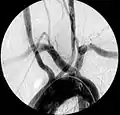

Angiografía mostrando arteria subclavia aberrante derecha